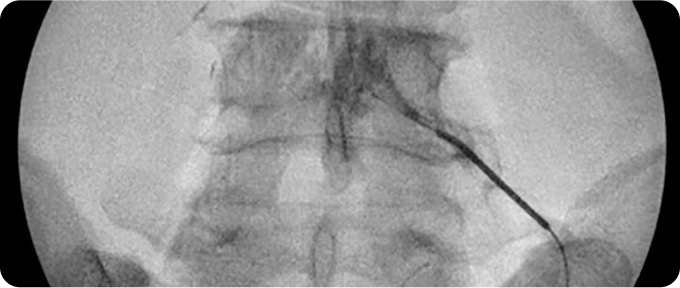

신경차단술 사진

1

신경차단술

신경에 약물을 주입해 염증과 통증을 완화하는 비수술적 치료입니다. 시술이 간단하고 비교적 안전하며, 즉각적인 통증 완화 효과를 기대할 수 있습니다. 허리디스크뿐만 아니라 척추관 협착증 등 다양한 신경통 치료에 사용됩니다. 다만, 일시적인 완화에 초점이 맞춰져 근본적인 문제 해결을 위해 추가 치료가 필요할 수 있습니다.